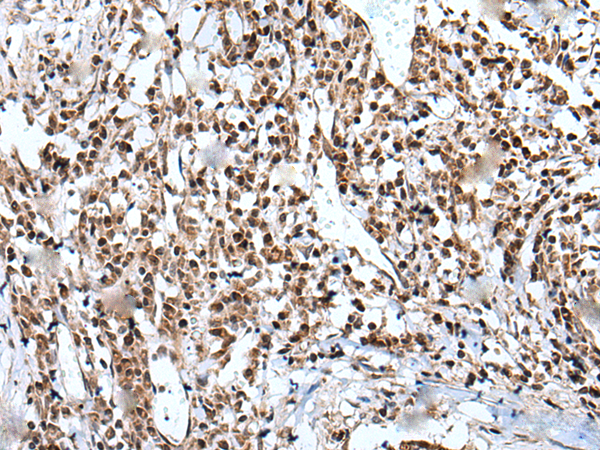

分类: 科研抗体货号: P12880别名: WAP14; dJ447F3.3应用: IHC反应种属: Human